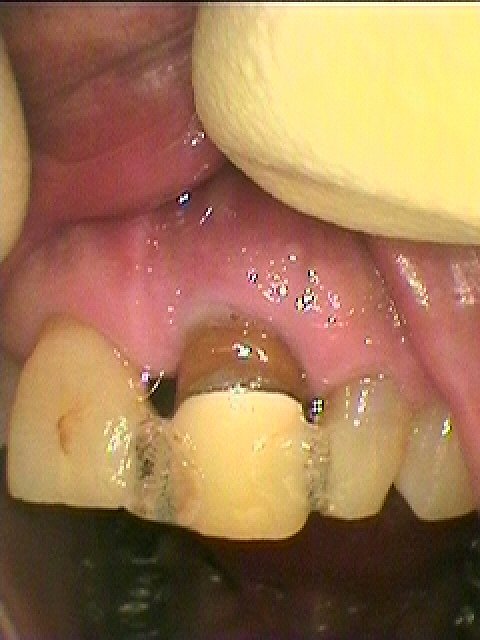

状態はこのようでした

両サイドに接着にて固定されていました

このように裏から診ても固定が、、、

固定は持っても数か月

また外れてはきます

デンタルレントゲンでも骨内には歯が埋まっていませんでした

抜歯を説明しています